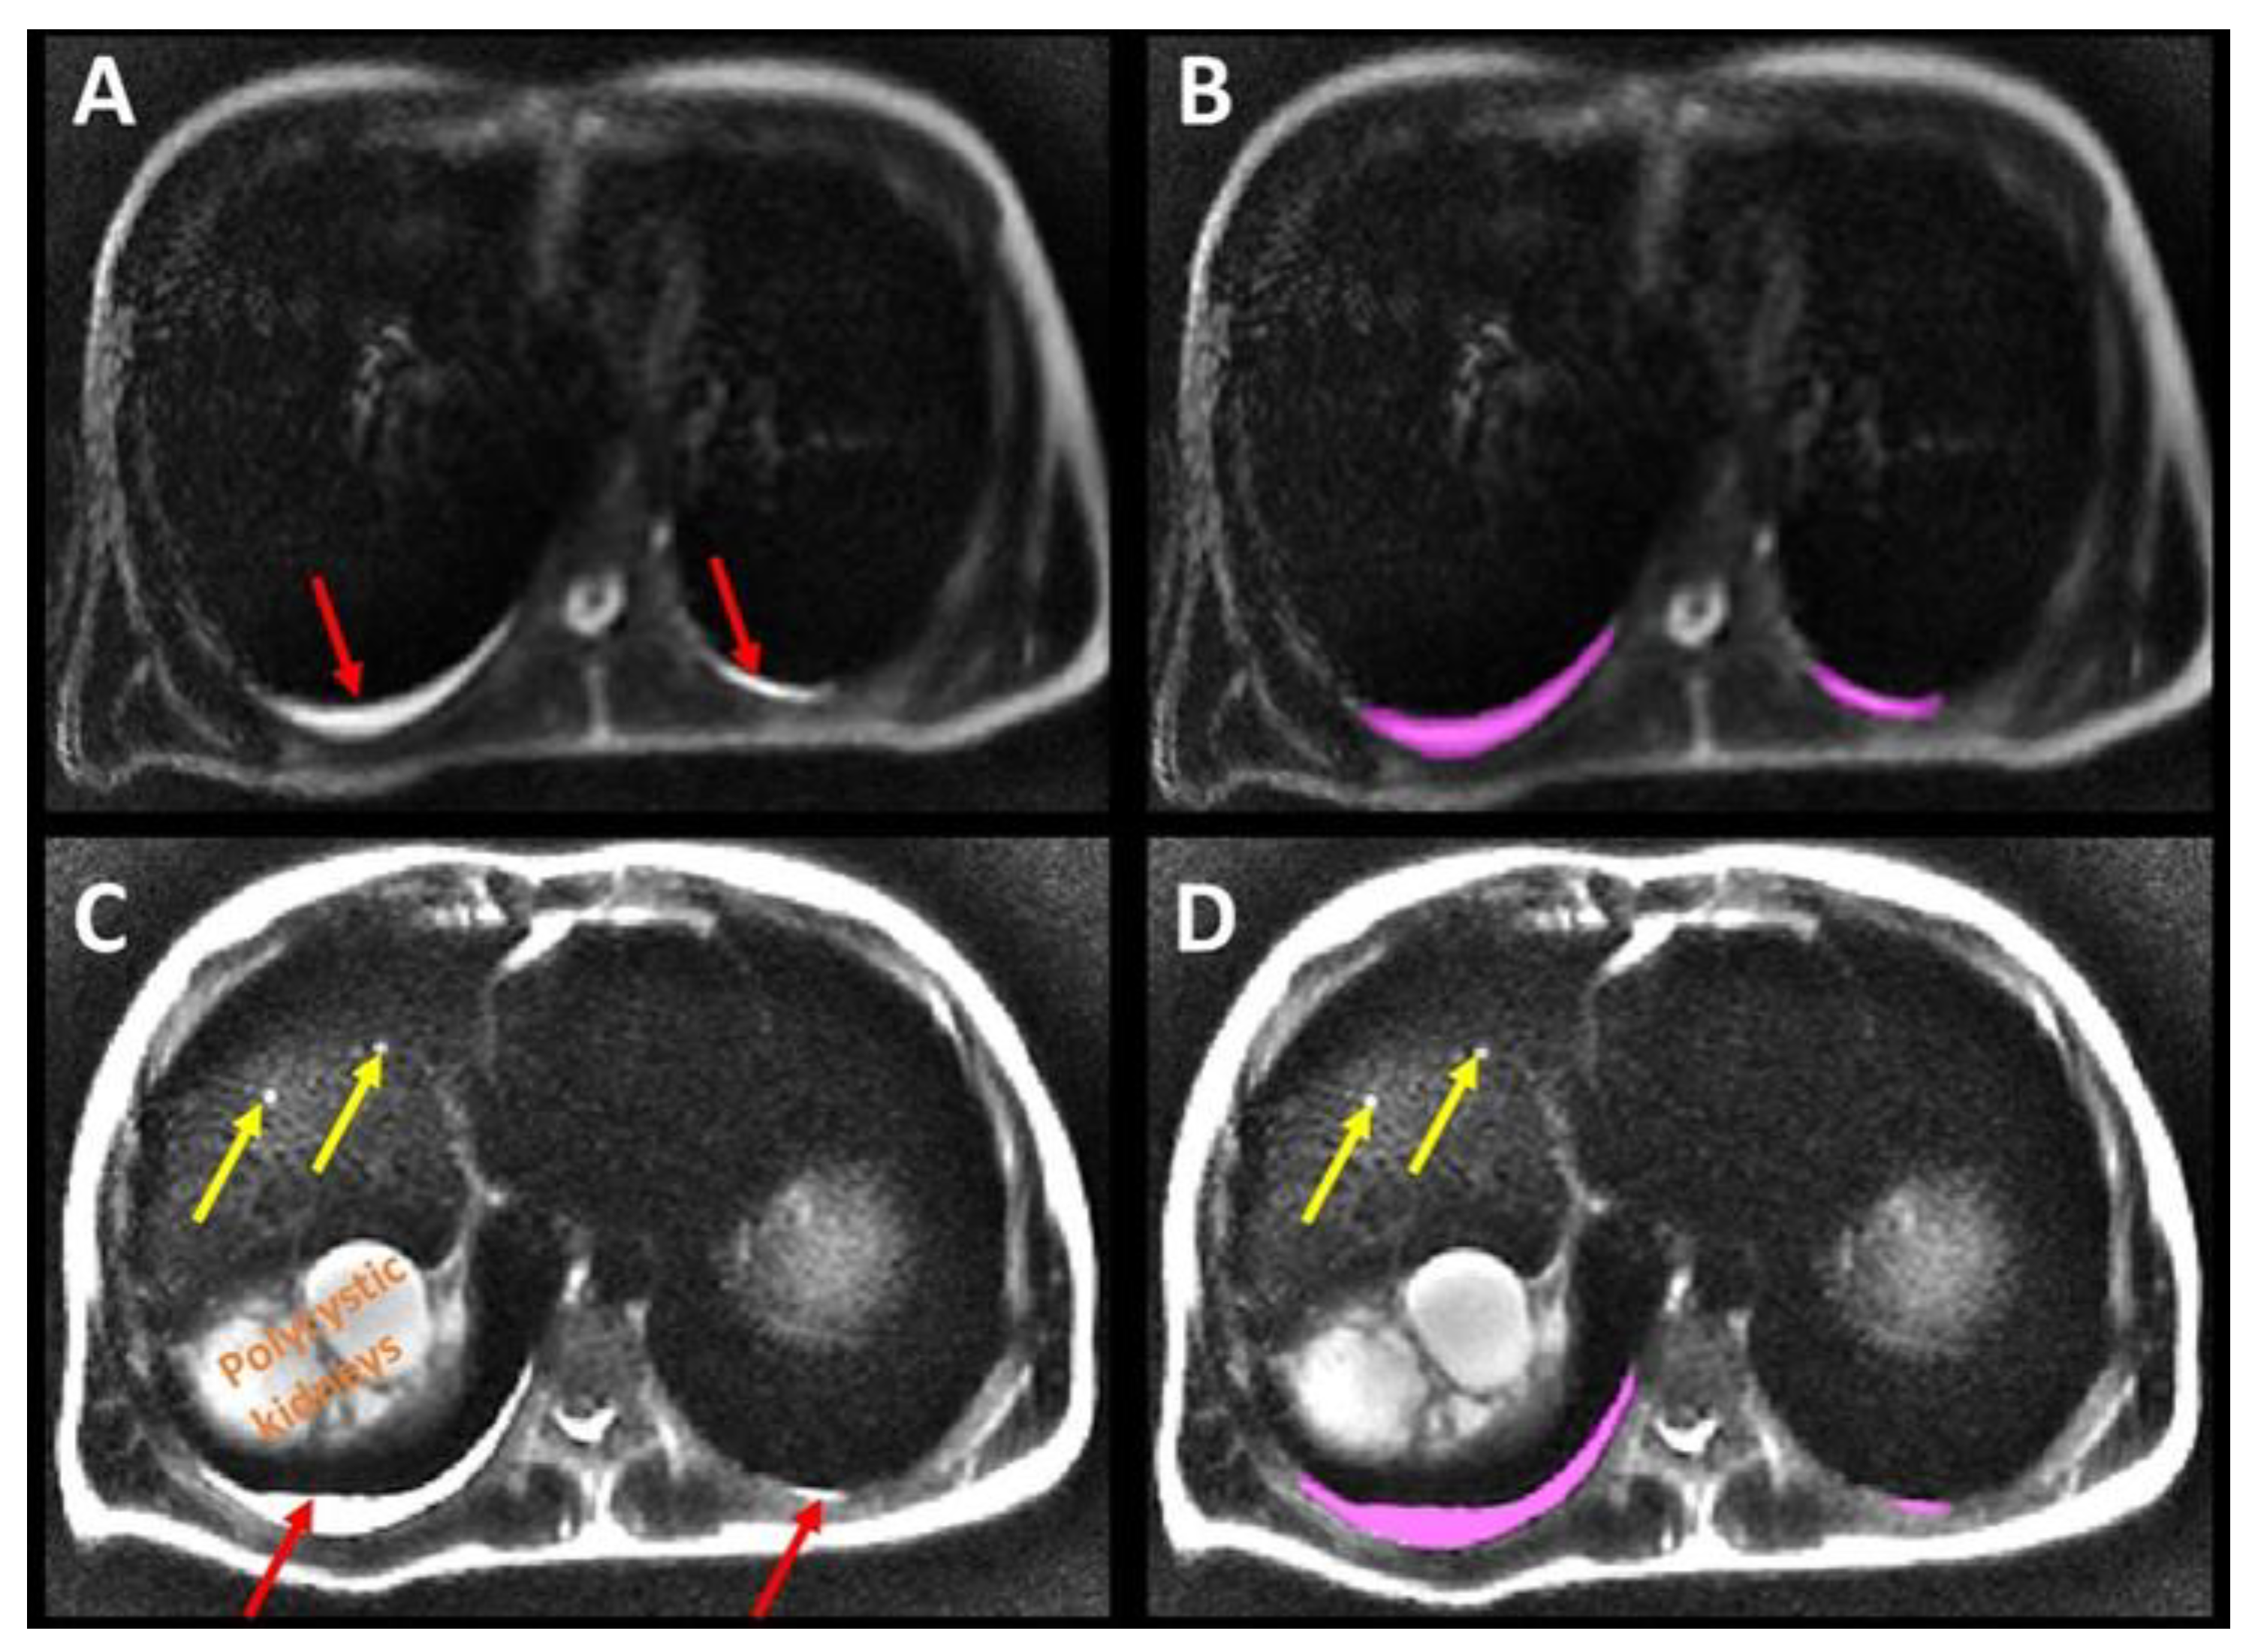

Axial T2 and DWI B0 MR images were analyzed by 3 independent observers (XY, XZ, MRP) blinded to all patient information. These observers had 6, 10 and 30 years of experience interpreting body MRI. Pleural effusion was designated as present when there was sufficient dependent fluid in the posterior-inferior thoracic pleural space to create a T2 bright fluid band, distinct from sub-pleural fat, at least 2 mm thick over a distance of at least 3 cm on at least two consecutive T2-weighted images. Pleural effusion was quantified using manual contouring to annotate dependent pleural fluid on every axial image using ITK-SNAP software, version 3.8.0 (downloaded 12 June 2019) (Figure 1).

Figure 1.

Axial T2 weighted images show pleural fluid (red arrows on (A,C)) which was measured by annotating the fluid, (B,D), in the thoracic cavity (pink label) to determine its volume. Liver cysts (yellow arrows) and the superior pole of the polycystic right kidney were also observed on the more inferior slices, (C,D).